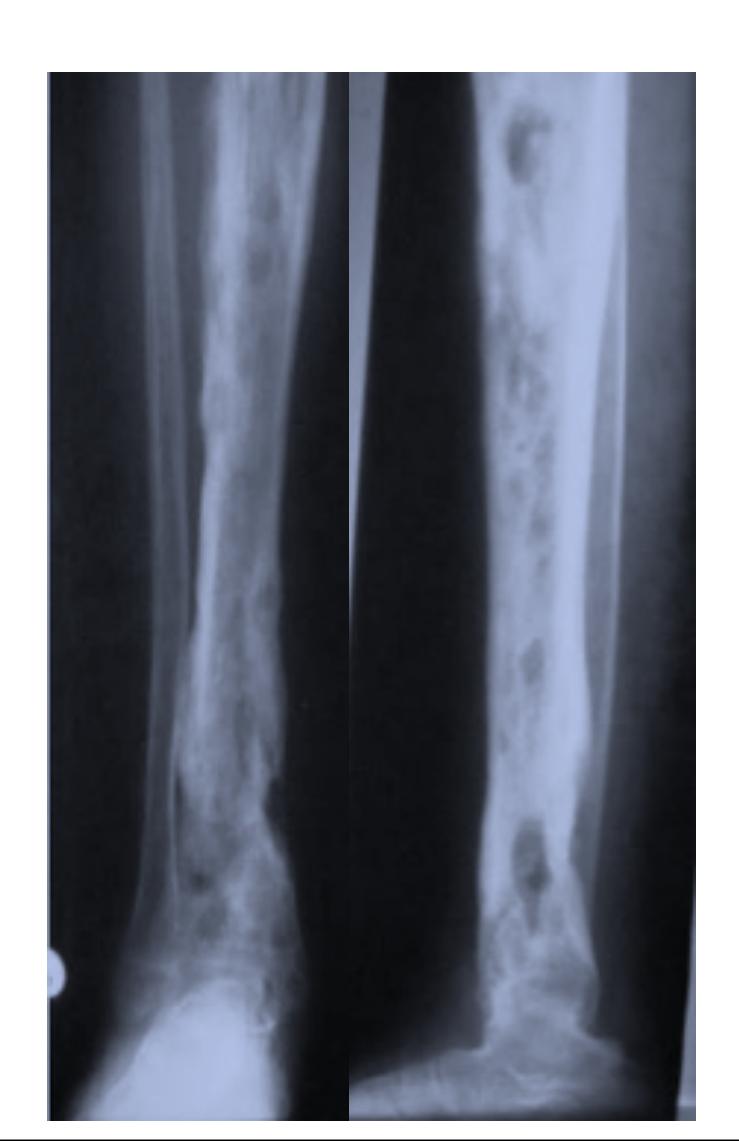

| Compartment Syndrome | Increased pressure within a closed fascial compartment, leading to reduced tissue perfusion, hypoxia, and irreversible muscle and nerve damage. Causes: Fractures (especially tibia/forearm), severe soft tissue trauma, arterial injury, burns, tight casts/dressings, post-ischemic reperfusion swelling, IV fluid extravasation, and bleeding disorders (e.g., hemophilia). High-Risk Notes: Pain may be absent in altered consciousness, children (monitor analgesia response), polytrauma, sedated/epidural cases, or concomitant nerve damage. Open fractures do not always decompress pressure. Gross/Clinical: -tense, shiny leg swelling with blisters in compartment syndrome.Imaging: - Intraoperative fasciotomy | History/Symptoms: Pain out of proportion to the injury (e.g., a “bursting” sensation), which is not relieved by analgesia. Clinical Features (The 5 P’s): - Pain with passive stretch (early, key sign; e.g., ankle dorsiflexion for leg, wrist for forearm). - Paresthesia (early). - Palpable tense swelling (shiny skin, blisters: clear=mild, serosanguinous=severe, bloody=worst; dusky/pallor skin). - Pallor, Paralysis, Pulselessness (late, ominous signs; pulses often palpable until late). Investigations: Primarily a clinical diagnosis (high suspicion key). Compartment pressure measurement can confirm: absolute pressure >30 mmHg or Delta Pressure (Diastolic BP - Compartment P) ≤ 25 mmHg. | Initial: ABCs, supplemental oxygen. Remove all circumferential dressings, casts (bivalve to skin), and splints. Elevate the limb to heart level (not above; higher reduces inflow). Correct any hypotension. Surgical: Urgent Fasciotomy if no response within 1h or confirmed pressure (prophylactic in high-risk like major osteotomy). Release all compartments/skin with long incisions; debride necrotic muscle via 4C’s (early: pink/red, soft, contracts/bleeds on pinch; late: dark, firm, no response); preserve neurovascular. Wound open (bulky dressing/splint, VAC, or boot-lace gradual closure); repeated inspections x48h; coverage in 3-5 days (skin graft usual; flap if nerves/vessels/bone exposed). | Cellulitis, Deep Vein Thrombosis (DVT), Arterial occlusion, Severe soft tissue injury without compartment syndrome; equivocal cases in polytrauma. | Complications: Volkmann’s ischemic contracture (permanent deformity, weakness, sensory loss, chronic pain). Contraindications (Fasciotomy): Confirmed >48h (irreversible damage, high infection risk from dead tissue); crush injuries with already necrotic muscle. |

| Open Fracture | A fracture with a breach in the overlying skin and soft tissues, creating communication with the external environment. All open fractures are considered contaminated (even small punctures; aka compound fracture). Causes: Can result from high-energy trauma (RTAs, falls, firearms; signs: degloving, crush syndrome, bone loss, segmental) or low-energy trauma. Contamination risk higher with farm/soil injuries, bites, delayed presentation (>12h), fecal/oral/soil/water exposure. Mechanism: Low/high velocity missiles (cavitation >300 m/s); in-out (cleaner) vs. out-in (dirtier). Gross/Clinical: ![]() | History: Mechanism of injury (energy, time, place, type/impact method), consciousness, wound size/bleeding amount, other injuries (often missed), tetanus status. Assessment: ATLS protocol (ABCDE) first (treat patient, not fracture; exclude shock/brain injury, monitor vitals; viscera exam: ribs=lungs/liver/spleen, pelvis=bladder/urethra). Examine wound (look/feel/move carefully post-splint), check distal neurovascular status, compartment syndrome. Photograph/remove gross contamination; cover with saline dressing. Classification (Gustilo-Anderson): - Type I: <1 cm wound, clean, minimal soft tissue. - Type II: >1 cm wound, moderate soft tissue (no stripping). - Type IIIA: Extensive soft tissue damage, but adequate bone coverage. - Type IIIB: Extensive soft tissue loss with periosteal stripping; bone exposed, requires flap coverage. - Type IIIC: Any open fracture with an arterial injury requiring repair. | Initial (ER): ATLS first. Cover wound with sterile saline-soaked dressing, splint limb, IV fluids (request blood if needed); traction if no distal pulse/deformity. Prophylaxis: Tetanus prophylaxis/serum and broad-spectrum IV antibiotics immediately (culture tissue/blood); clean major contamination. Surgical: Urgent debridement/irrigation within 6-12h (“Dilution is the solution to pollution”; pulse-irrigate 3-6-9L saline; excise non-viable tissue/foreign material, trim skin edges, remove dead muscle/detached bone, preserve N/V). Stabilization: external fixator (preferred severe; replace with cast post-infection); internal if clean/minimal. Wound closure delayed (primary if small/clean; secondary if contaminated/large). Early soft tissue cover. | The diagnosis is typically obvious. Key: Classify severity; identify associated injuries like compartment syndrome, vascular damage, or high-energy signs (e.g., crush). Differentials for contamination: Primary (field debris) vs. secondary (post-fixation if poor debridement). | Complications: Infection (cellulitis, osteomyelitis, chronic with sequestra/drainage, gas gangrene), tetanus; higher with delay/exposure/bites. - embolisms fat, thrombi others.. Case Insight: Unconscious patient (e.g., open tibia post-RTA): ABCDE/cervical collar, distal pulses/traction, admit for debridement; ankle fall: Splint post-ABC, assess neurovascular. |